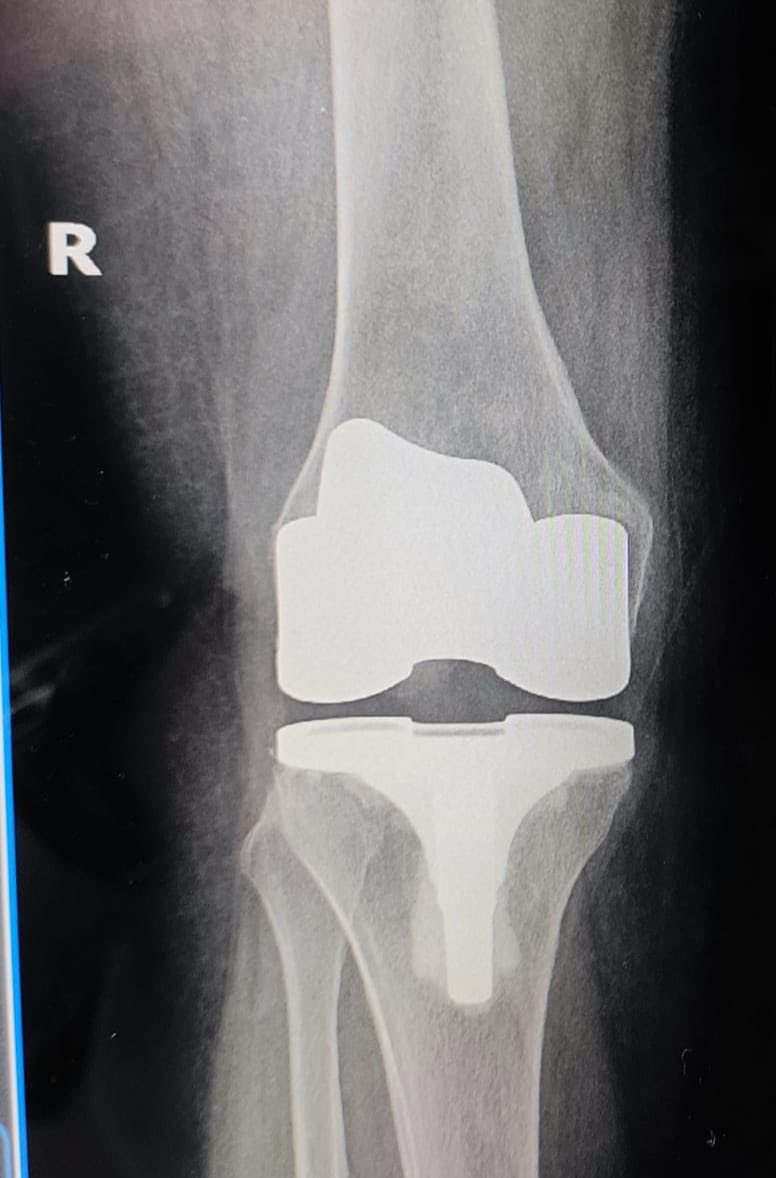

An elderly lady closely related to me had severe osteoporosis of knees.

We did TKR for both her knees. She went back home in 4 days. Came back for follow up in a week completely able to walk by herself & also climbing stairs with some support.

Her X Ray showed fracture inches above TKR